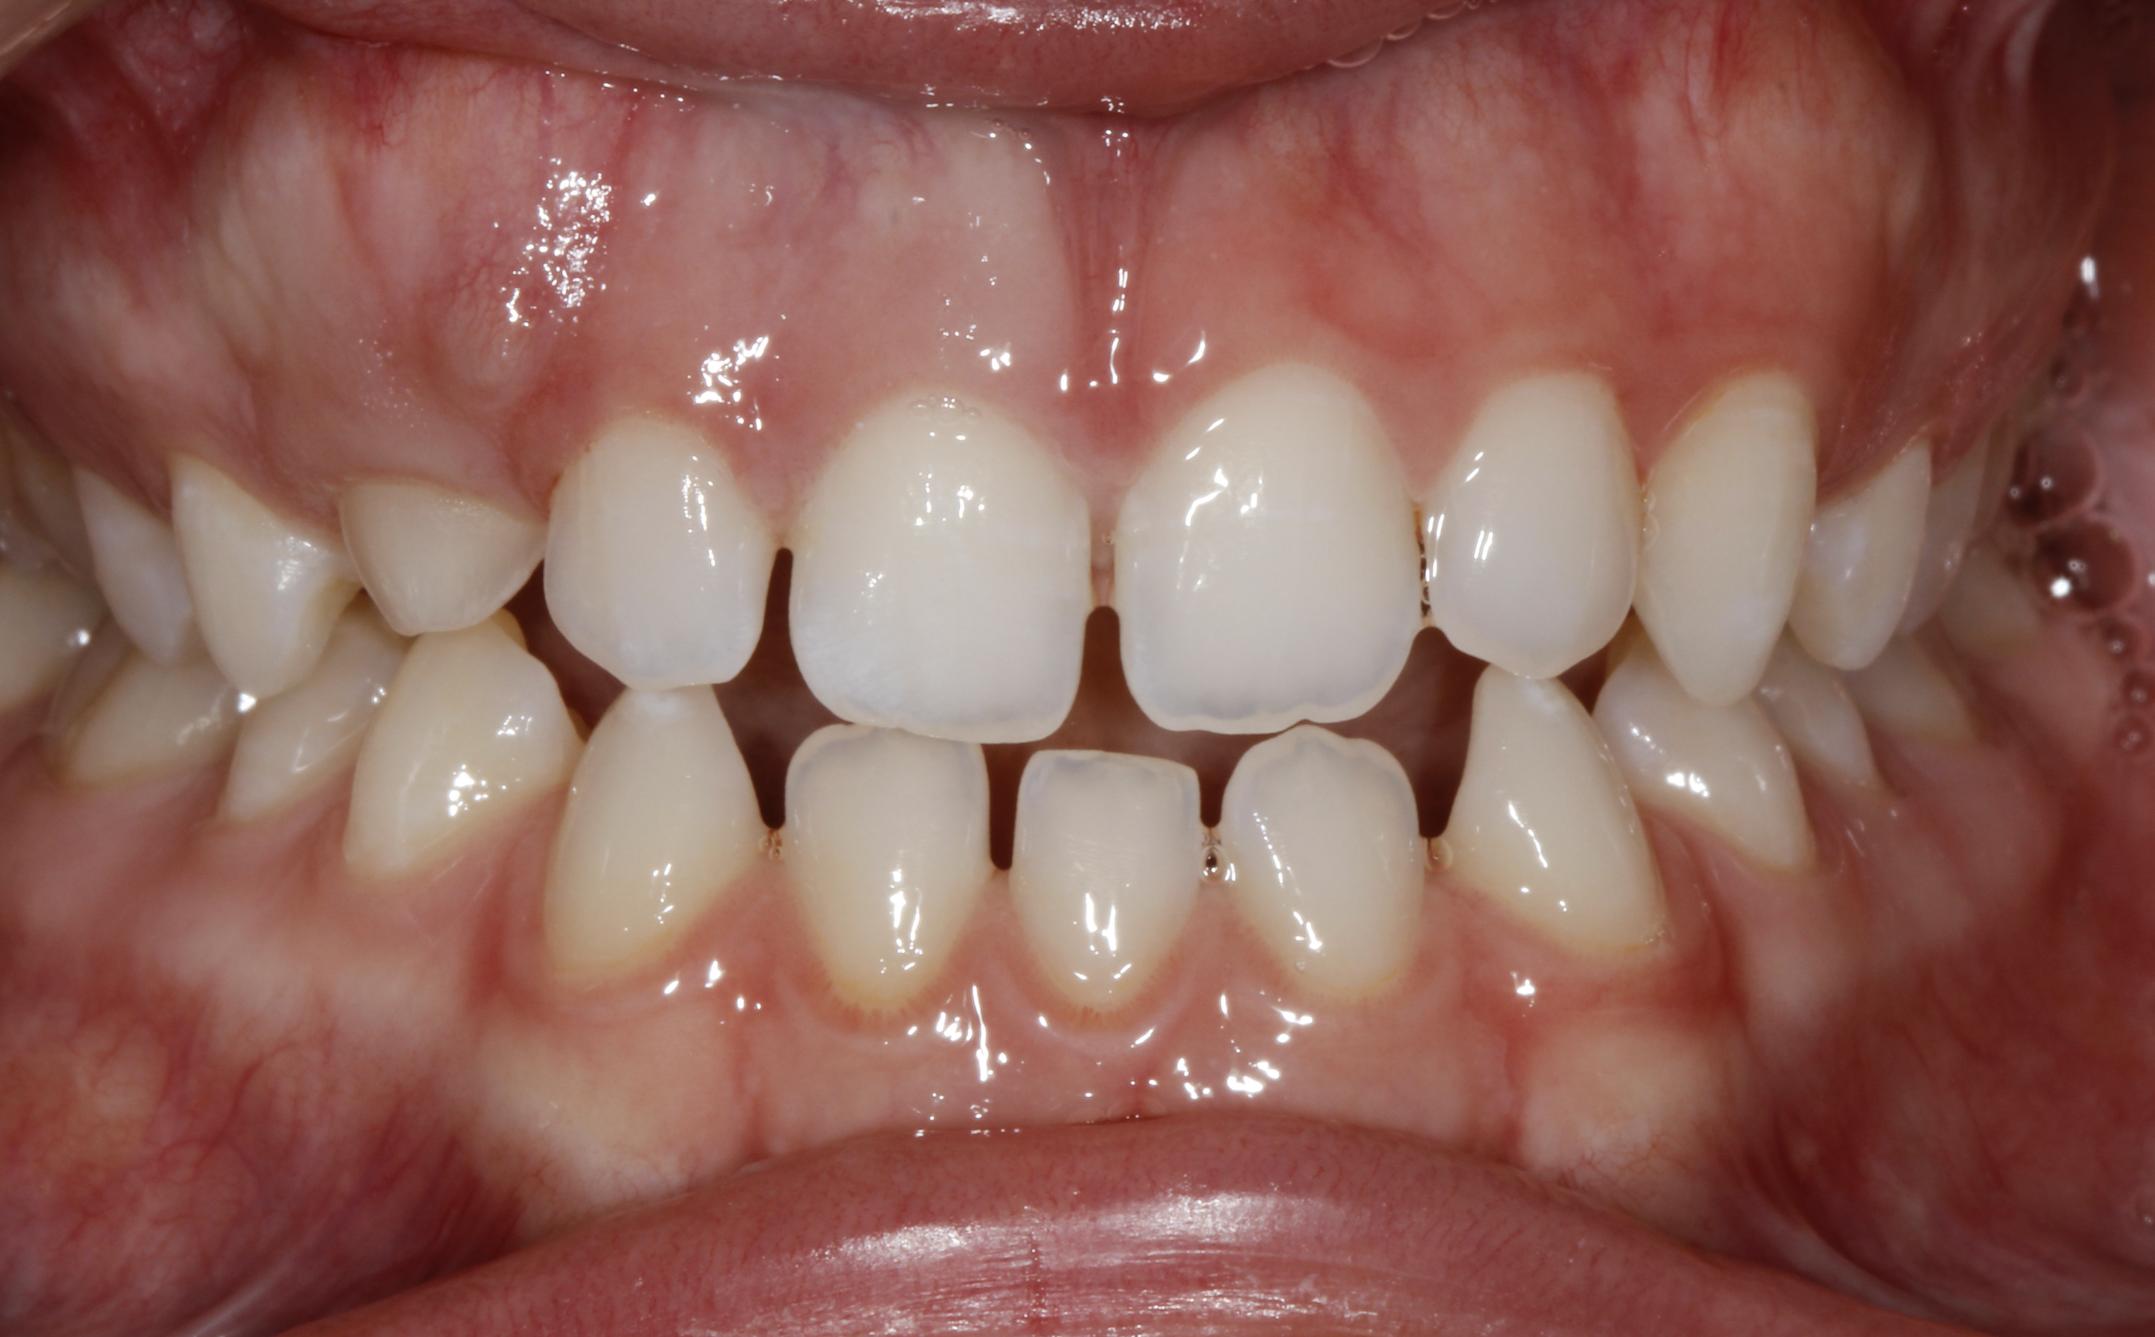

Esthetic Crown Lengthening

Before After

Before Image

After Image